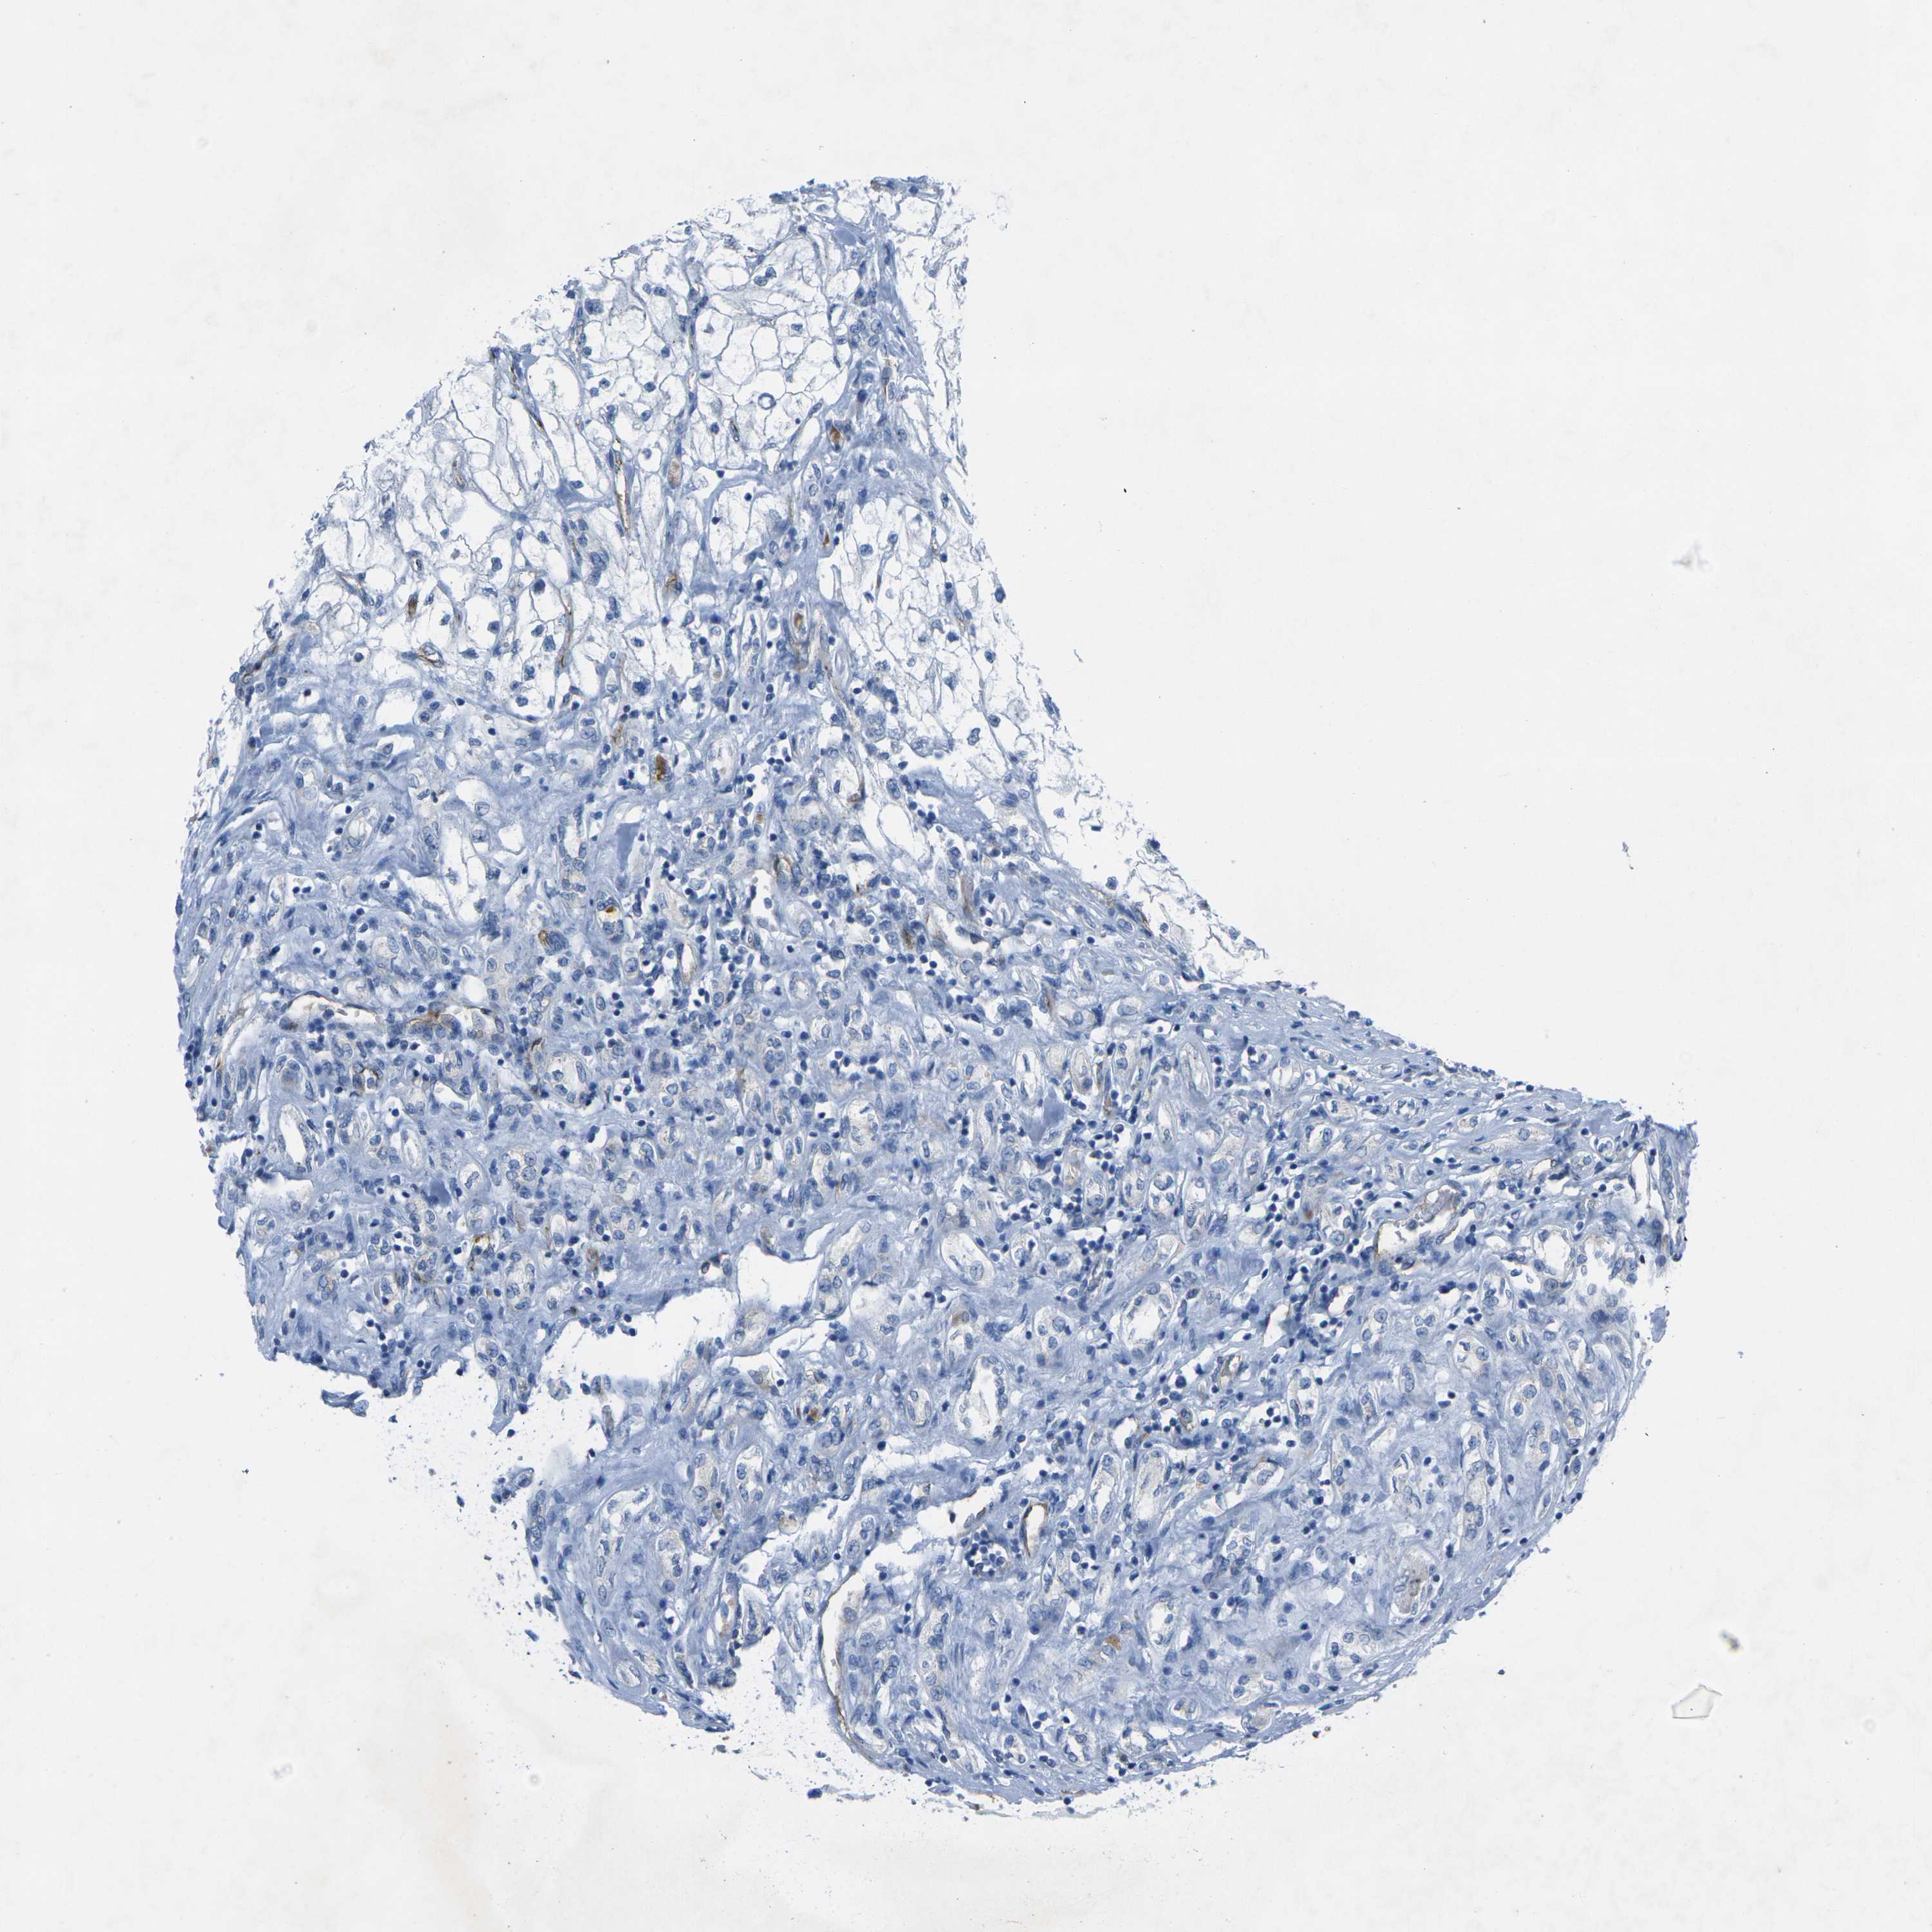

HSPA12B is validated prognostic, high expression is favorable in Kidney Renal Clear Cell Carcinoma (validation)

Best expression cut offi

Based on the FPKM value of each gene, patients were classified into two groups and association between prognosis (survival) and gene expression (FPKM) was examined. The best expression cut-off refers the FPKM value that yields maximal difference with regard to survival between the two groups at the lowest log-rank P-value. Best expression cut-off was selected based on survival analysis .

When clicking on this number, the vertical dashed line indicating cut-off, the interactive survival plot, and the Kaplan-Meier curve will be adjusted to show results based on the best expression cut-off.

: 3.53

TCGA RNA samplesi

RNA-seq data is reported as average FPKM (number Fragments Per Kilobase of exon per Million reads), generated by the The Cancer Genome Atlas (TCGA) .

Normal distribution across the dataset is visualized with box plots, shown as median and 25th and 75th percentiles. Points are displayed as outliers if they are above or below 1.5 times the interquartile range. FPKM values of the individual samples are presented next to the box plot.

Average pTPM 7.7

Number of samples 100